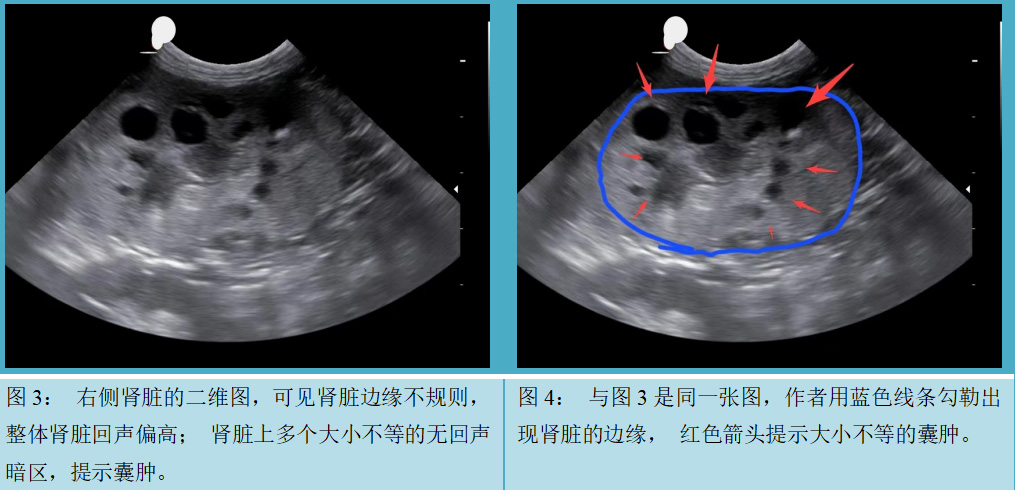

患者名叫TT,是一只去势的公加菲猫,7岁,体重1.9kg。TT在3月龄做腹部彩超体检时,发现肾上有多个很小的无回声暗区,提示多囊肾。当时猫的精神、食欲、大小便都没有异常,所以没有接受任何治疗,TT在5月龄的时候被现在的主人收养。大约3岁的时候,猫开始表现不太正常,每天喜欢睡觉,不爱玩耍。最近一年TT明显消瘦,体重从最重时候的4.5kg降到1.9kg. 同时食欲很差,被毛粗乱,经常腹泻。主人带TT到多个医院检查,进行腹部X片,血常规和生化检查等,但没有明显异常发现。经人推荐,TT转诊到作者的医院做腹部彩超检查,发现肾脏上多个囊肿(图1,图2,图3,图4,图5和图6),胃肠道未见明显异常,西医诊断为多囊肾。建议主人做其他相关检查,主人不想再给动物采血,也不想用其他西医方案,但是主人愿意尝试针灸。